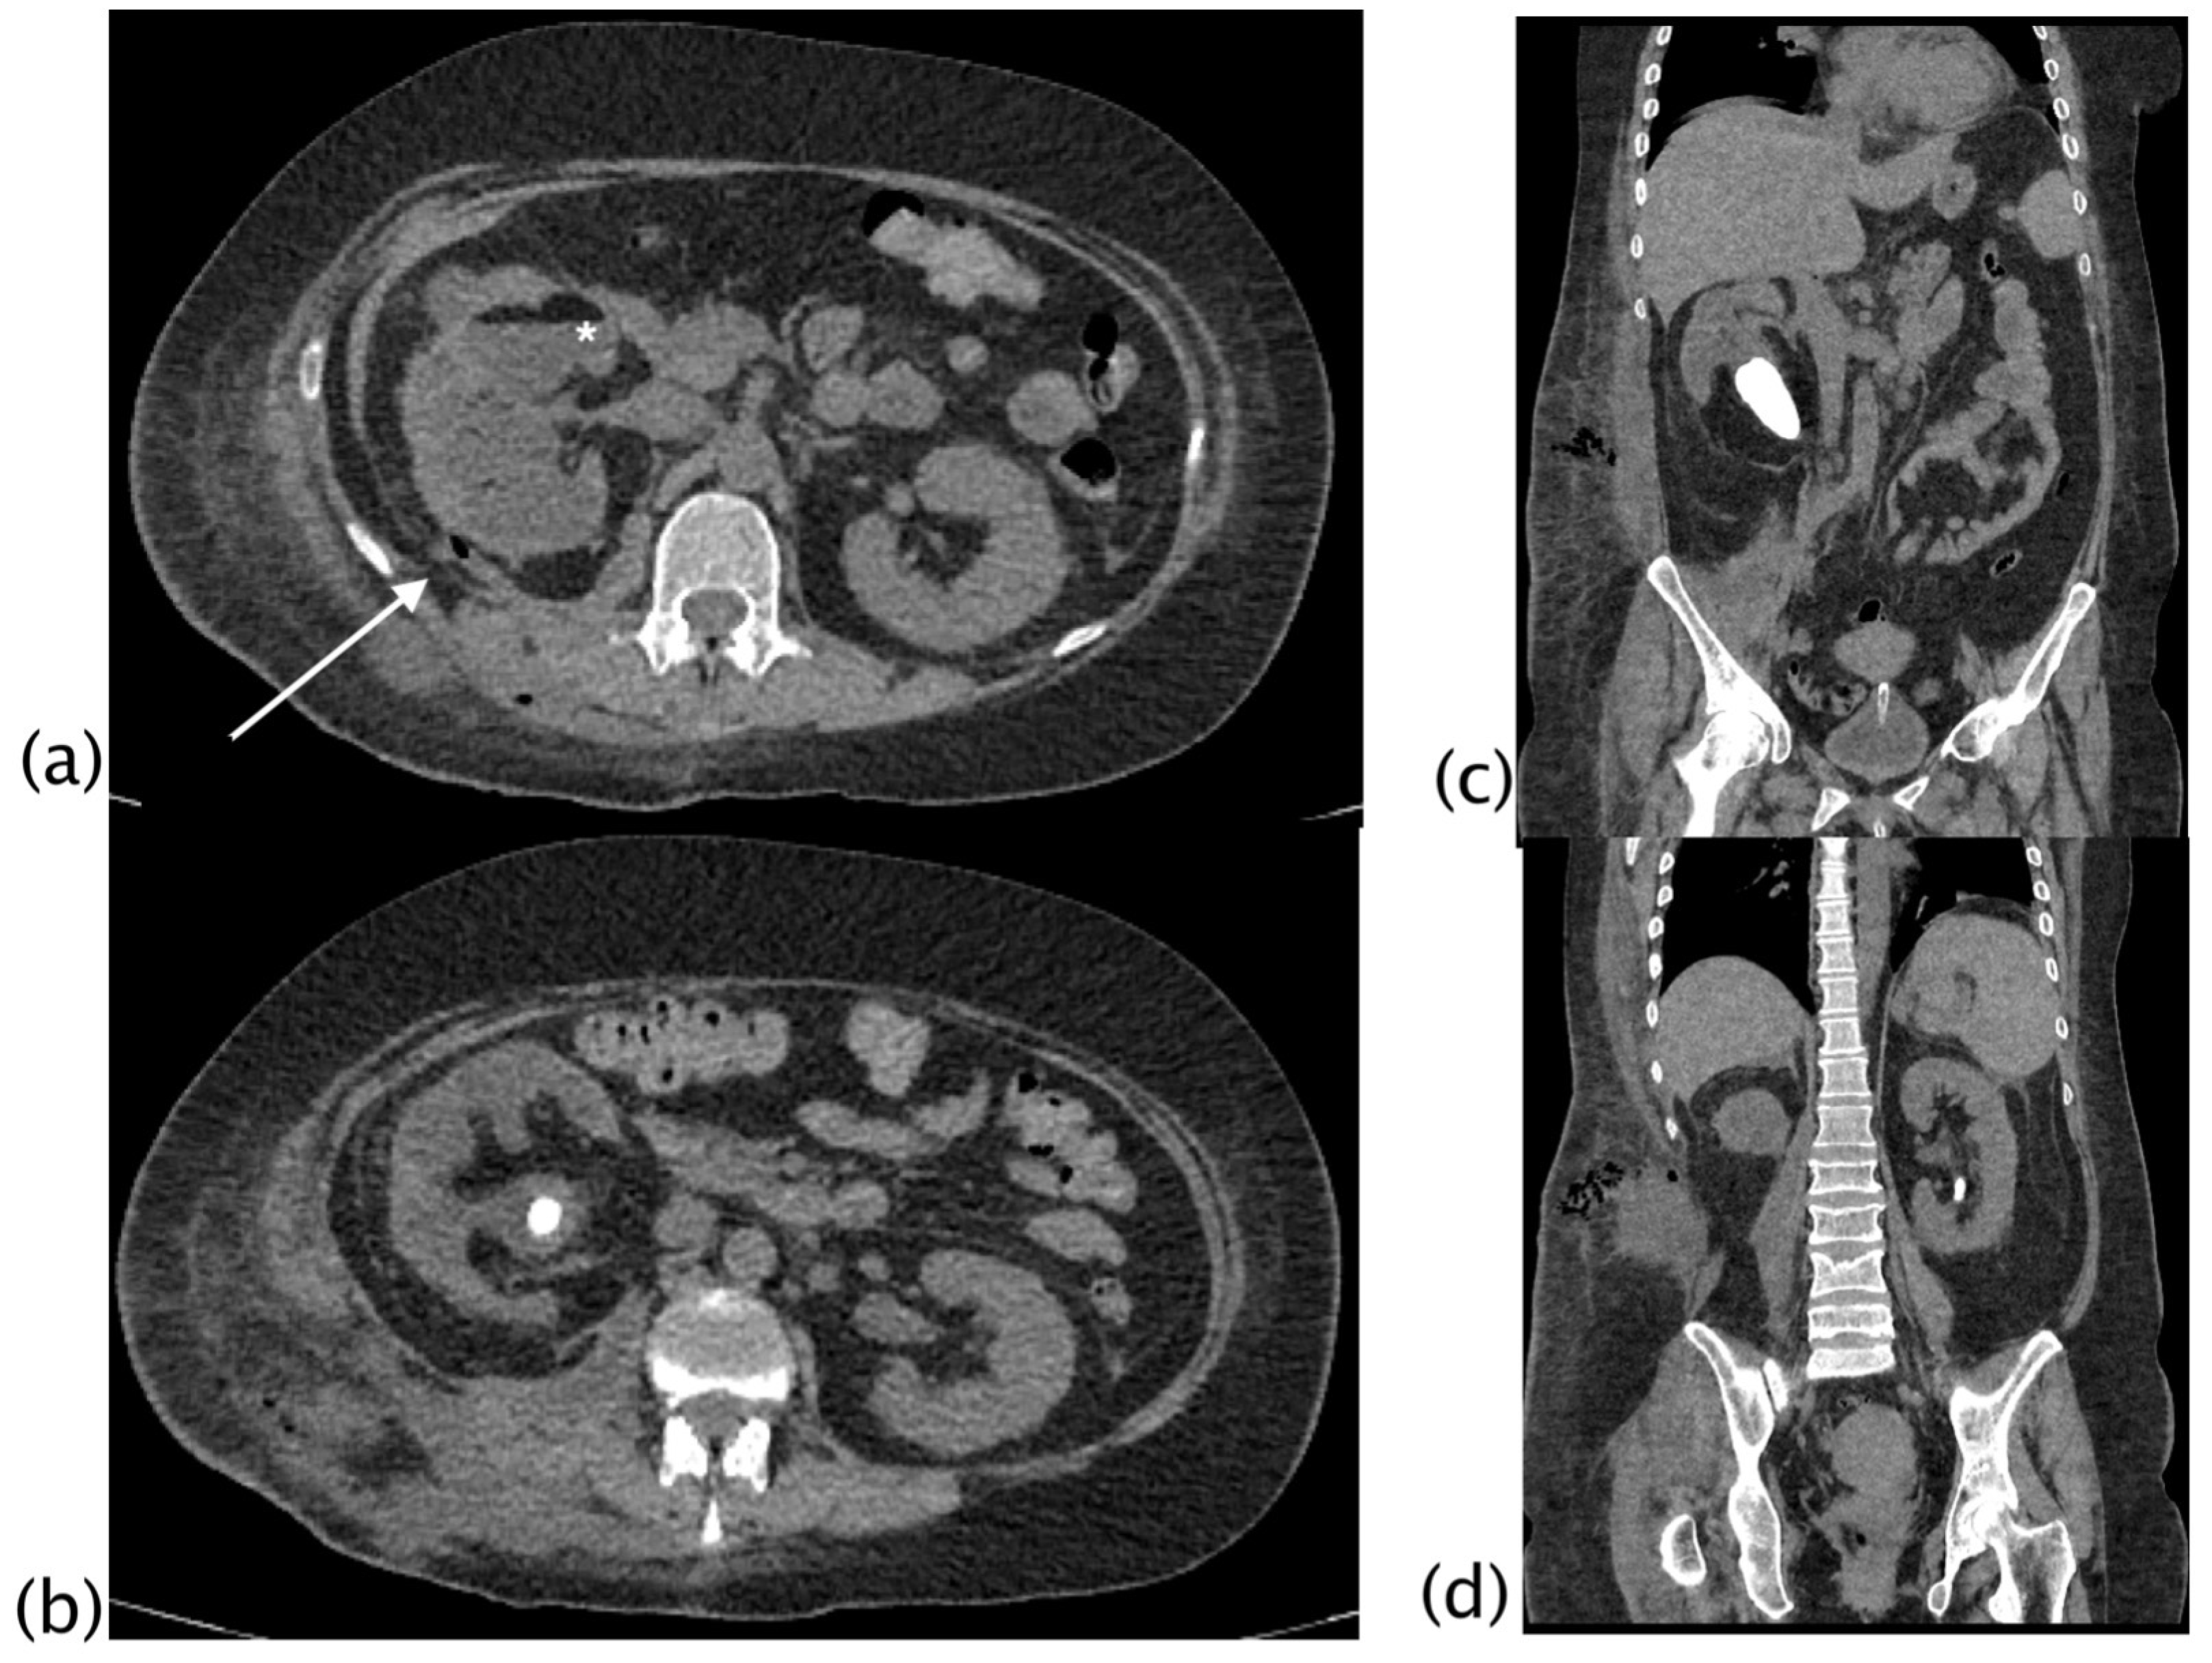

Figure 4.

Xanthogranulomatous pyelonephritis Stage III—pararenal form. Non-enhanced CT examination: axial (a,b) and coronal MPR reconstruction (c,d). The right kidney is increased in volume with reduced parenchymal representation and a “contracted” appearance of the renal pelvis. The renal parenchyma is extremely thinned and characterized by the presence of multiple hypodense areas that cannot be better characterized without contrast agent. (a) Within the fluid collection at the anterior middle third of the kidney, a “layer” characterized by fluid (white asterisk) and adipose density (above white asterisk) can be noted, named “xanthoma” and characteristic of the disease. Staghorn lithiasis is present. No significant thickening of the perirenal fat tissue is noted. On the posterior profile of the kidney, a fistulous via with hydro-gas content is visible ((a), white arrow; (b)), which carries posteriorly into the psoas and dorsal muscles with fluid collection in the context of the muscle bundles. The fistulous via terminates in the subcutaneous flank soft tissues where fluid collection with gas is present ((d), MPR coronal).